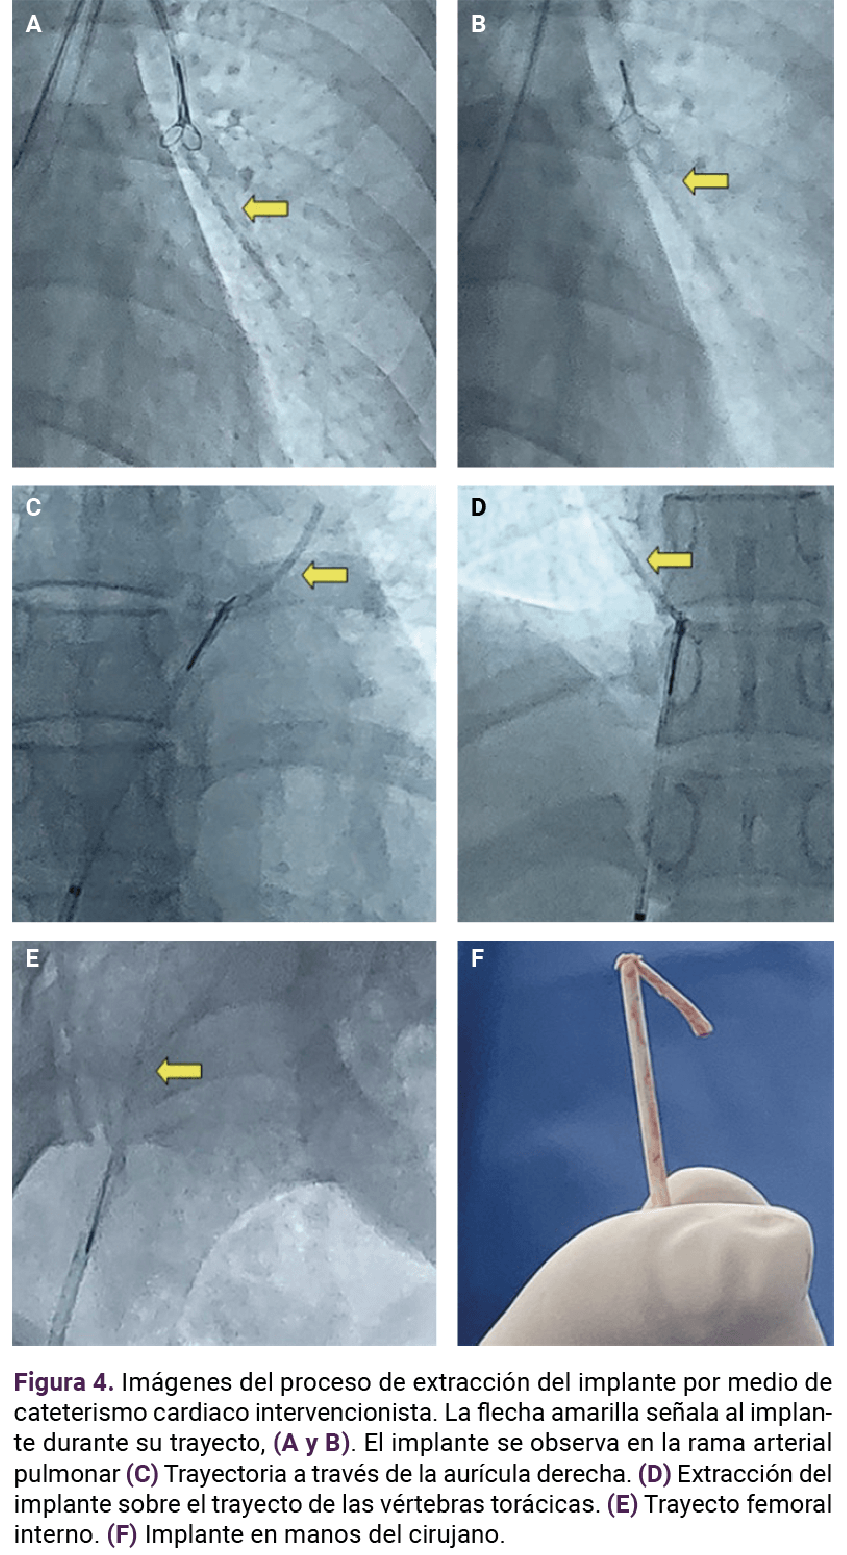

Paciente de 25 años, con menarquia a los 13 años, e inicio de la vida sexual activa a los 18 años, dismenorrea, ciclos irregulares, un embarazo, un parto y aplicación posparto de un implante subdérmico de etonogestrel. Tres años después de la colocación acudió a la unidad de planificación familiar para el retiro del implante, con extracción fallida (no se logró palparlo). Se practicaron estudios de imagen complementarios para su ubicación, entre ellos una radiografía de tórax (Figura 1) en la que se visualizó una imagen hiperintensa en el área del parénquima pulmonar.

<strong>Figura 1</strong>

Figura 1